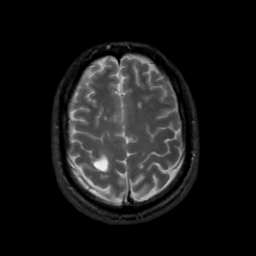

MR Study #10, April 28, 1991 -- Slice #39

[Home][Help][Clinical][Tour 1][Tour 2] Slice 39